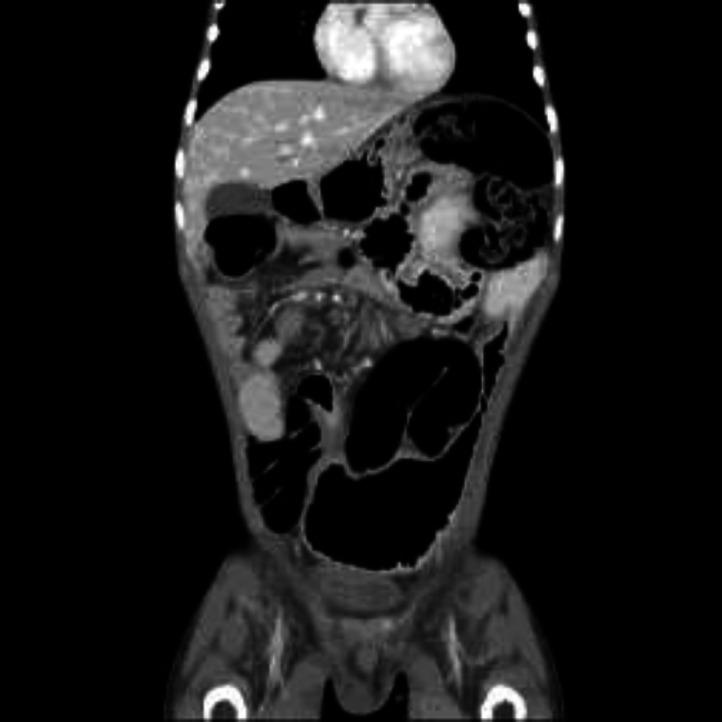

We report this unusual presentation of small intestine volvulus in an 11-year old Nigerian boy who first presented only with anasarca. While being investigated for the cause of the anasarca, he developed features of acute abdomen thought to be spontaneous bacteria peritonitis initially. He had surgery where the diagnosis of small intestine volvulus was made.

我们报告一名11岁尼日利亚男孩小肠扭转的这一不寻常表现,他最初仅表现为全身性水肿。在对全身性水肿的病因进行检查时,他出现了急腹症症状,最初被认为是自发性细菌性腹膜炎。他接受了手术,术中诊断为小肠扭转。